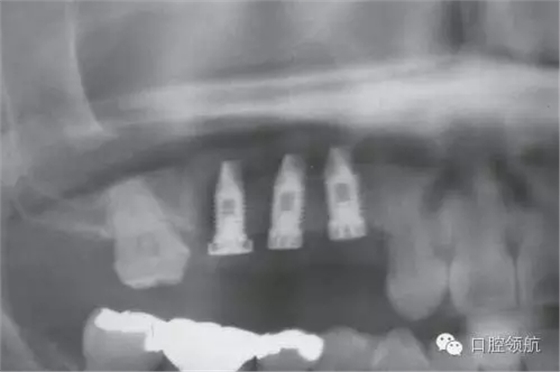

圖4 術后即刻的曲面斷層影像

術后1周準備拆線時,發(fā)現覆蓋螺絲部分露出。遂延期1周拆線,并每2天清洗一次創(chuàng)面,為了在暴露的覆蓋螺絲周圍有正常軟組織環(huán)繞,拆線后每隔2~3天來院,用生理鹽水清潔軟毛牙刷去除軟垢,保持創(chuàng)面清潔穩(wěn)定(圖6~圖10)。

圖8 術后7年6個月的曲面斷層影像